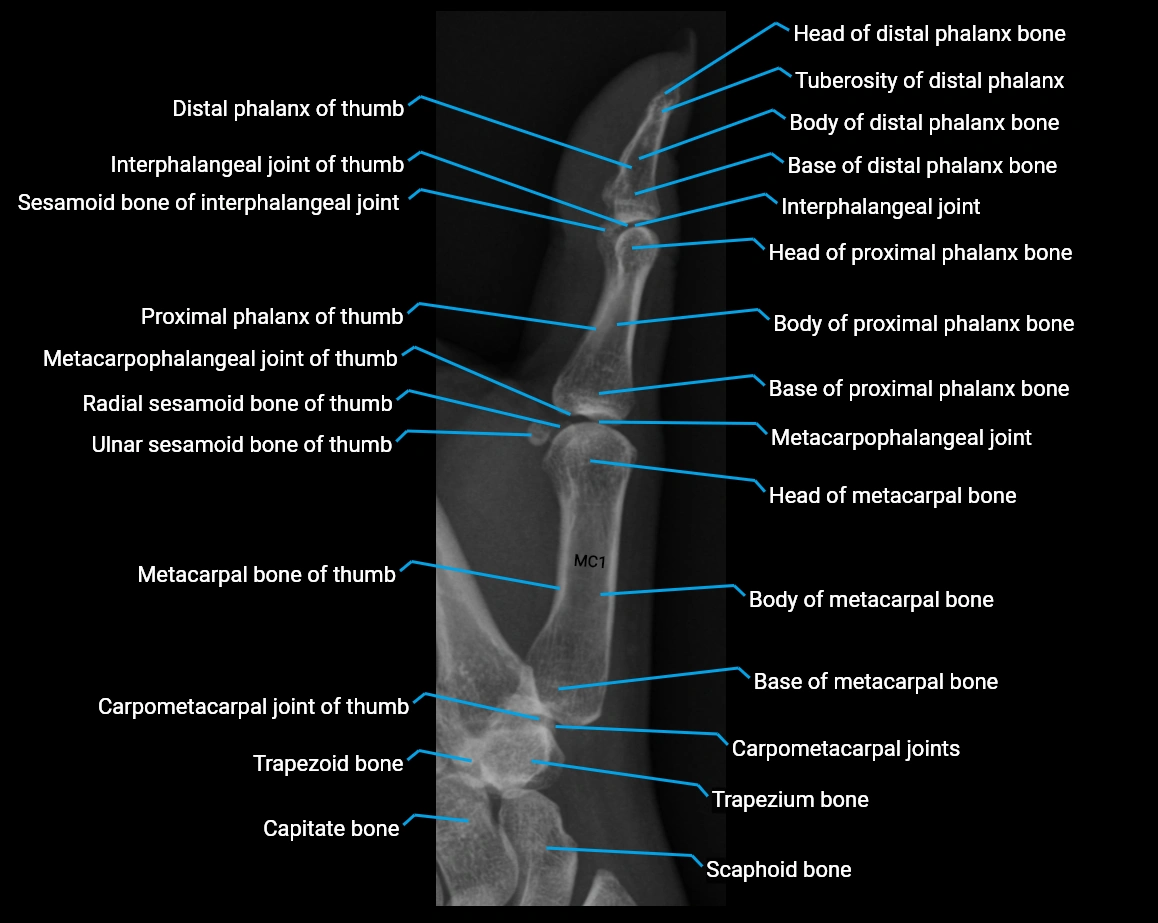

X Ray image

image